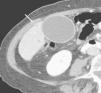

La TC helicoidal permitió, además, llevar a cabo un estudio detallado de los pequeños vasos arteriales y venosos peripancreáticos24-26 (fig. 2), mostrando mejores resultados que la angiografía por sustracción digital en el diagnóstico de la invasión vascular por cáncer de páncreas27. La valoración de estas pequeñas estructuras vasculares mejora el rendimiento de la TC en la estadificación tumoral28,29. La posibilidad de reconstruir en diferentes planos del espacio las imágenes axiales obtenidas ha sido evaluada por algunos autores30,31, obteniendo un mayor rendimiento de la TC para determinar la invasión vascular, fundamentalmente venosa, cuando las secciones transversas se interpretan en combinación con las reconstrucciones multiplanares que cuando se interpretan únicamente las secciones transversas (92-96% frente a 69-70%) (fig. 3).

Fig. 3.--Estudio de tomografía computarizada con contraste endovenoso en fase venosa portal en un paciente con neoplasia de páncreas. Masa heterogénea mal definida en el cuerpo pancreático. (A) Sección axial que no permite identificar el eje esplénico-mesentérico-portal. (B) La reconstrucción multiplanar oblicua coronal, orientada en el plano del confluente venoso demuestra de forma clara la disminución del calibre de la vena porta en su origen y de la vena mesentérica superior en su confluencia con la vena porta (puntas de flecha), que permite establecer el diagnóstico de infiltración venosa local, mostrando la longitud del segmento venoso afectado.